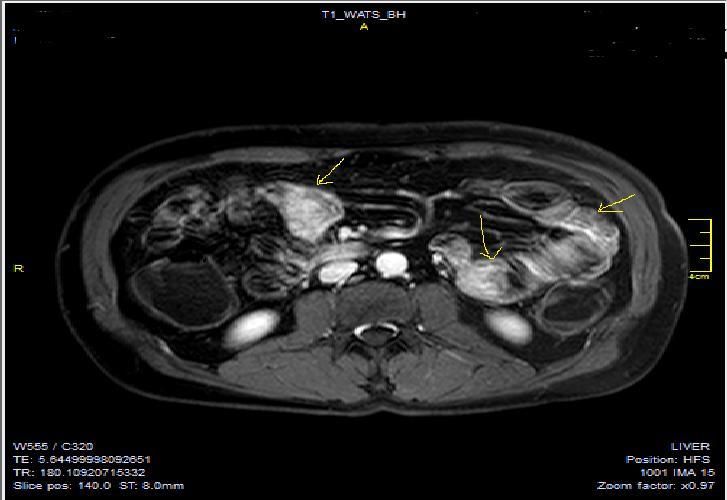

Figure 4a.Mucosal involvement and lack of opacified ileal segments with loss of intestinal folds and increased bowel wall thickness due to Crohn’s disease on T2W coronal sequence after OCA, presented at 37 years old male with moderate Crohn’s disease.

Figure 4b.Mucosal, luminal and bowel wall involvement in Crohn’s disease with skipped lesions, seen at T2W axial image after OCA, presented at 45 years old male with severe inflammatory disease.